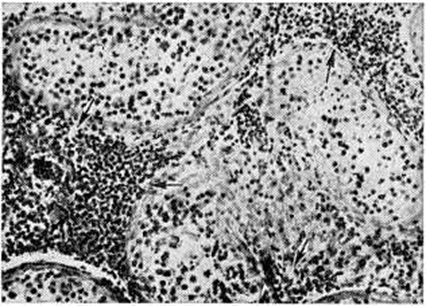

Географическое распространениеВ прошлом все войны сопровождались Сыпной тиф эпидемический Обычно от эпидемий Сыпной тиф эпидемический войска несли потери, намного превышающие боевые потери. Так, в русско-турецкую войну 1768— 1774 годы в русских войсках от Сыпной тиф эпидемический умерло около 44 тысяч человек, а от оружия погибло около 35 тысяч Наполеоновские войска разнесли Сыпной тиф эпидемический по всей Европе; в Германии в 1813—1814 годы Сыпной тиф эпидемический переболело 2—3 миллионов человек. Первая мировая война привела к высокому подъему заболеваемости Сыпной тиф эпидемический в ряде государств. Например, в Сербии в 1915 год погибло от Сыпной тиф эпидемический свыше 150 тысяч человек Во время Гражданской войны и иностранной интервенции и в последующие годы (1918— 1922) на территории СССР, по данным различных исследователей, Сыпной тиф эпидемический переболело от 7 до 20 миллионов человек Вторая мировая война также сопровождалась высокой заболеваемостью Сыпной тиф эпидемический во многих странах. Так, от эпидемий Сыпной тиф эпидемический в 1942—1944 годы пострадали страны Сев. Африки. Затем с войсками Сыпной тиф эпидемический проник в Италию (эпидемия в Неаполе), поразил Польшу, Германию, Румынию и другие, широко распространился в Иране и Ираке. Эпидемии Сыпной тиф эпидемический наблюдались и на территории СССР, временно оккупированной немецко-фашистскими войсками. Так, при освобождении от оккупации Великолукского района среди населения было выявлено 5205 больных, а на территории Невельского и соседнего районов — 5806. Заболеваемость Сыпной тиф эпидемический несколько повышалась и в тыловых районах СССР, что было связано с эвакуацией больших масс населения из западных районов страны на восток, со скученностью эвакуированных людей, живших нередко в не приспособленных для жилья помещениях (почти 70% больных приходилось на эвакуированных), однако болезнь не получила широкого распространения. ЭтиологияВозбудителем сыпного тифа является риккетсия Провачека — Rickettsia prowazekii da Rocha-Lima, 1916, относящаяся к роду Rickettsia семейство Rickettsiaceae. Риккетсии грамотрицательны, размером 0,3—0,6 × 0,8—2,0 микрометров (иногда до 4,0 микрометров). В отличие от других видов риккетсий (смотри полный свод знаний) у риккетсий Провачека при культивировании наблюдается полиморфизм — они принимают форму кокков и палочек (смотри полный свод знаний: рисунок 1 к статье Риккетсии). Риккетсии Провачека при окраске по Гимзе или по Здродовскому (модификация окраски Маккиавелло) красного цвета и хорошо видны в световом микроскопе; их ультраструктура (смотри полный свод знаний: рисунок 2 к статье Риккетсии) сходна с субмикроскопической организацией грамотрицательных бактерий. Размножаются риккетсии Провачека поперечным бинарным делением, время генерации при оптимальных условиях около 12 часов Риккетсии Провачека содержат протеины, углеводы, липиды, фосфолипиды, РНК, ДНК; в клеточной стенке обнаружены мурамовая и диаминопимелиновая кислоты, сахара, аминосахара, 17 аминокислот. Риккетсии Провачека, являясь внутриклеточными паразитами, располагаются в цитоплазме. Они хорошо размножаются в желточном мешке куриного эмбриона и на различных клеточных культурах; в культуре фибробластов куриного эмбриона образуют бляшки. Для риккетсий Провачека характерно наличие весьма лабильного токсина. Они чувствительны к действию высокой температуры, влажности, многих химический веществ. Вместе с тем они могут длительно сохраняться при низкой температуре в белковых субстратах, а также в высушенном виде. Особое значение имеет возможность длительного сохранения риккетсий в сухих фекалий зараженных вшей. Риккетсии Провачека чувствительны к действию ряда антибиотиков (левомицетина, тетрациклинов, эритромицина, рифампицина). Из лабораторный животных наиболее восприимчивы к риккетсиям Провачека хлопковые крысы и морские свинки (при всех способах заражения), белые мыши высокочувствительны к интраназальному заражению. ЭпидемиологияЕдинственным источником инфекции является больной человек, который остаётся источником заражения в течение 20— 21 дня, то есть последние два дня инкубации, весь лихорадочный период (до 17 дней) и первые два дня апирексии. До последних двух дней инкубационного периода и с третьего дня апирексии возбудителей Сыпной тиф эпидемический в крови больного, как правило, не обнаруживают. Переносчиком возбудителей инфекции при Сыпной тиф эпидемический служит платяная вошь (Pediculus vestimenti). Головная и лобковая вши (Pediculus capitis и Phthirus pubis) также могут переносить возбудителя, но их эпидемиологические роль по сравнению с платяной вошью незначительна (смотри полный свод знаний: Вши). Риккетсиями Сыпной тиф эпидемический вошь заражается при кровососании на больном; способной передавать возбудителя она становится лишь на 5—6-й день, реже — на 9 — 10-й день. В это время происходит накопление возбудителя и внедрение его в эпителий кишечной стенки вши. Однажды заразившись, вошь способна передавать возбудителя до конца своей жизни (живет до 45—46 дней). Своему потомству насекомые риккетсий не передают. Возбудители Сыпной тиф эпидемический, размножаясь и накапливаясь в большом количестве в эпителиальных клетках кишки вши, разрывают эти клетки и выделяются в просвет её кишечника. В других частях тела вши, в том числе в слюнных железах и в сосательном аппарате, риккетсий не содержится. Заражение человека Сыпной тиф эпидемический происходит следующим образом. Когда зараженная вошь прокалывает кожу человека и начинает сосать кровь, её кишечник постепенно наполняется кровью и одновременно происходит акт дефекации, при котором на поверхность кожи человека выделяются фекалии с большим количеством риккетсий. Укус вши сопровождается зудом. Человек, расчесывая место укуса, втирает заразный материал в образовавшиеся ссадины. Таким образом, возникновение и распространение Сыпной тиф эпидемический всегда связано с вшивостью (смотри полный свод знаний: Вши), сопровождающей ухудшение санитарный состояния тех или иных групп населения. Сыпной тиф эпидемический в прошлом нередко назывался военным, голодным, тюремным тифом. Сами эти названия говорят о том, что наибольшее распространение Сыпной тиф эпидемический получал во время войн, голода и других социальных потрясений, когда ухудшалось материальное положение народа, усиливалась миграция населения, наблюдался недостаток белья, мыла и тому подобное К Сыпной тиф эпидемический восприимчивы люди всех возрастов. В условиях распространения заболевания риску заражения наиболее подвержены работники транспорта, персонал бань, прачечных, дезинфекторы. В прошлом наблюдалась повышенная заболеваемость среди медперсонала. Внедрение в практику санобработки больных, дезинсекции вещей больного и санитарный транспорта снизило эту опасность. Выраженная сезонность Сыпной тиф эпидемический для средних широт (февраль — апрель) определяется увеличением контактов среди населения за счёт скученности в жилищах в холодное время года. ПатогенезРиккетсии Провачека, попадая в кровь человека, быстро проникают в клетки эндотелия кровеносных сосудов, где размножаются и выделяют эндотоксин. Под действием эндотоксина эндотелиальные клетки набухают, происходит их десквамация и разрушение. Риккетсии вновь поступают в кровь, часть из них гибнет, высвобождая эндотоксин, а остальные вновь проникают в клетки эндотелия сосудов. Такого рода процесс без видимых клинические, проявлений продолжается до тех пор, пока не наступит достаточное количественное насыщение организма риккетсиями и их эндотоксином. Последний обладает вазодилатационным эффектом, особенно в системе мелких сосудов — капилляров, прекапилляров, артериол, венул, в которых нарушается микроциркуляция (смотри полный свод знаний) вплоть до образования паралитической гиперемии и замедления тока крови. В результате этого создаются условия, способствующие развитию гиалиновых тромбов в местах паразитирования риккетсий, где произошла деструкция эндотелия сосудов, с последующим образованием в органах и тканях специфической гранулемы (смотри полный свод знаний). Такого рода изменения в сосудах выявляются с 6—8-го дня болезни практически во всех органах и тканях, но больше всего они выражены в головном мозге, в коже, конъюнктивах глазных яблок, надпочечниках, миокарде, почках. Известную роль в патогенезе Сыпной тиф эпидемический играет и аллергический компонент, но суть его пока не ясна. В процессе болезни наступает специфическая иммунная перестройка организма, ведущая в итоге к выздоровлению. Риккетсии могут обнаруживаться в органах и тканях в последние дни инкубации, во время всего лихорадочного периода и в первые дни апирексии. В организме больных возбудитель может длительно сохраняться и после клинического выздоровления, это явление ещё недостаточно изучено. Обратное развитие морфологический изменений начинается с 18—20-го дня от начала болезни и завершается в основном к концу 4-й недели, а иногда и позже. Патологическая анатомияПатологическая анатомия сыпного тифа изучена главным образом отечественными исследователями И. В. Давыдовским, А. П. Авцыным, Ш. И. Криницким и другие На коже можно обнаружить следы сыпи в виде неясно контурированных пятен и точек розового, коричневатого, красного цвета. Более стойким признаком является конъюнктивальная сыпь (смотри полный свод знаний: Киари — Авцына симптом). Отмечается серозный менингит (смотри полный свод знаний), полнокровие ткани головного мозга, значительное полнокровие и увеличение массы лёгких (в 2—4 раза), увеличение размеров селезенки в 2—3 раза. При гистологический исследовании обнаруживают характерное поражение кровеносных сосудов капиллярного типа, получившее название эндотромбоваскулита, с набуханием и деструкцией эндотелия, слущиванием его клеток в просвет сосуда и формированием пристеночного или обтурирующего тромба (смотри полный свод знаний). Эти изменения сопровождаются пролиферацией адвентициальных гистиоцитов, к которым примешиваются немногочисленные нейтрофилы и лимфоидные элементы, что наряду с очаговой гиперемией капилляров лежит в основе формирования сыпнотифозной розеолы. Углубление деструктивных изменений в сосудах, диапедез эритроцитов характеризуют превращение розеолы в сыпнотифозную петехию. Аналогичные изменения можно обнаружить в различных органах и системах. В головном мозге (смотри полный свод знаний) сыпнотифозные узелки, впервые описанные Л. В. Поповым (1875), обнаруживаются в варолиевом мосту (мост головного мозга), ножках мозга, коре головного мозга, базальных ядрах, таламусах (зрительных буграх), мозжечке, гипоталамусе, задней доле гипофиза. Как правило, сыпнотифозных узелков нет в белом веществе полушарий головного мозга. Сыпнотифозные узелки в ткани головного мозга построены из клеток микроглии, к к-рым, как правило, примешиваются сегментоядерные лейкоциты (рисунок 1). Важное диагностическое значение имеет скопление сыпнотифозных узелков в продолговатом мозге, в частности в области его нижних оливных ядер. Количество таких узелков в центральная нервная система зависит в основном от длительности лихорадочного периода. В случае смерти на 2—4-й неделе болезни их обнаруживают в 100%. У переболевших сыпнотифозные узелки регрессируют. Сохраняющиеся в более поздние периоды болезни гистологические изменения могут быть диагностическим признаком перенесённого в прошлом Сыпной тиф эпидемический В центральная нервная система отмечается, как правило, гиперемия и стазы (нередко с формированием гиалиновых тромбов в капиллярах серого вещества), периваскулярные (главным образом перивенозные) муфты из плазматических клеток, диффузная и очаговая пролиферация микроглии. Этот патогистологический комплекс (стазы, характерные сыпнотифозные узелки в сером веществе головного мозга, особенно в продолговатом мозге, муфты из плазматических клеток вокруг мелких вен, пролиферация макрофагов в мягкой оболочке головного мозга) даёт право считать, что каждый-случай Сыпной тиф эпидемический сопровождается энцефалитом (смотри полный свод знаний: Энцефалиты), выраженность которого широко варьирует. Следует отметить, что в противовес указанным сосудистым и интерстициальным изменениям в центральная нервная система тяжёлое альтеративное поражение нервных клеток и нервных волокон для типичного течения Сыпной тиф эпидемический не характерно.

В симпатической и в меньшей степени в парасимпатической нервной системе при Сыпной тиф эпидемический наблюдается интерстициальный ганглионит с образованием узелков и инфильтратов, пролиферацией капсульных клеток. Тяжёлые деструктивные ганглиониты и специфические невриты встречаются как исключение. Характерным признаком Сыпной тиф эпидемический является также и интерстициальный миокардит (смотри полный свод знаний), проявляющийся очаговой, реже диффузной инфильтрацией стромы миокарда плазматическими клетками в сочетании с большим или меньшим образованием сыпнотифозных узелков и слабыми изменениями кардиомиоцитов (рисунок 2). Отмечается также сыпнотифозный интерстициальный орхит (рисунок 3) и интерстициальный нефрит (смотри полный свод знаний), которые могут быть очаговыми и диффузными. Поражение почечных клубочков проявляется главным образом гиалиновым тромбозом (иногда с некрозом отдельных петель) и много реже очаговым гломерулонефритом (смотри полный свод знаний). При плохом уходе за полостью рта у больных, находящихся в прострации, наблюдаются гнойный паротит (смотри полный свод знаний) и воспаление подчелюстной железы (смотри полный свод знаний). Изредка встречаются небольшие инфильтраты, узелки и поражения сосудов желудка. Размеры печени увеличены, паренхима её мало изменена. Слизистая оболочка дыхательных путей обычно полнокровна. Закономерное увеличение массы лёгких и их вишнево-красный цвет обусловлены главным образом депонированием крови в малом круге кровообращения. Возможен отёк легких. В мышцах гортани при микроскопическом исследовании наблюдается специфический интерстициальный миозит. Относительно редки перихондрит (смотри полный свод знаний) и флегмона гортани (смотри полный свод знаний). Весьма частым осложнением являются пневмонии (обычно лобулярные, но изредка и лобарные). Своеобразную форму поражения более крупных сосудов представляют собой секторальные и реже циркулярные некрозы стенки артерий, сопровождающиеся явлениями плазморрагии (смотри полный свод знаний) и периваскулярными пролифератами. Они встречаются не ранее 3-й недели болезни, но могут наблюдаться и позже. Изредка они могут быть причиной тяжёлых локальных гемодинамических расстройств — размягчения мозга, сопровождающегося параличами (смотри полный свод знаний: Параличи, парезы), афазией (смотри полный свод знаний), клинические, картиной поперечного миелита (смотри полный свод знаний) и другие Эти же изменения в артериях сетчатки могут обусловить слепоту (смотри полный свод знаний). Очевидно, они же лежат в основе довольно редких внезапных кровоизлияний в мозг у реконвалесцентов. Эти поздние деструктивные изменения крупных артериальных стволов связывают с гиперсенсибилизацией организма. Интерстициальные инфильтраты могут наблюдаться в стенке аорты и в мышечной оболочке крупных вен. В эндокринных железах (гипофиз, надпочечники, щитовидная железа) можно обнаружить характерные сыпнотифозные узелки и очаговые инфильтраты. В селезёнке (смотри полный свод знаний) выявляют резко выраженную пролиферацию гистиоцитов и плазматических клеток, десквамацию их и более крупных макрофагальных элементов, а также скопление сегментоядерных лейкоцитов, умеренные отложения гемосидерина. В цитоплазме макрофагов и эндотелиальных клеток обнаруживают азурофильную зернистость, морфологически неотличимую от риккетсий. В костном мозге (смотри полный свод знаний) также отмечают пролиферацию базофильных гистиоцитов и реже образование специфических периваскулярных узелков. ИммунитетИнфекционных процесс при Сыпной тиф эпидемический сопровождается развитием стойкого и длительного иммунитета. Повторные заболевания редки. В работах П. Ф. Здродовского с сотрудники (1972) показано, что иммунитет при Сыпной тиф эпидемический возникает вскоре после заражения. В течение лихорадочного периода иммунитет нестерильный, то есть развивается в присутствии микроба, а после перенесенной болезни, по мнению многих исследователей, стерильный, сохраняющийся длительно (до 40 лет). Ряд исследователей — К. Н. Токаревич, Г. С. Мосинг, В. М. Колотов, Р. А. Пшеничный с сотрудники, Ш. Николау и Константинеско (N. Constantinesco) допускают возможность длительного переживания риккетсий в организме перенесшего Сыпной тиф эпидемический человека. С учётом этого К. Н. Токаревич и Г. С. Мосинг рассматривали возникший после Сыпной тиф эпидемический иммунитет как нестерильный. Возможна активная иммунизация вакциной, приготовленной из культуры риккетсий Провачека (смотри полный свод знаний: ниже Профилактика). Клиническая картинаИнкубационный период колеблется от 5 до 25 дней, чаще 10—12 дней. Различают легкое, среднетяжелое, тяжёлое и очень тяжёлое течение болезни. При наиболее типичном среднетяжелом течении Сыпной тиф эпидемический, наблюдаемом у 60—65% больных, болезнь начинается с повышения температуры, появления чувства жара, головокружения и головной боли, слабости, лёгкого познабливания и потливости, ломоты во всем теле, жажды и потери аппетита. Все эти признаки быстро нарастают, особенно головная боль, которая с первых дней становится мучительной. Появляются бессонница, боль в мышцах и суставах, обостряются восприятия, отмечаются раздражительность и беспокойство, иногда переходящее в состояние эйфории и возбуждения; возможно состояние заторможенности. Наблюдается выраженная гиперемия лица и конъюнктив — красные глаза на красном лице, гиперемия кожи шеи и верхней части туловища, лёгкая амимия, одутловатость лица, умеренный цианоз губ. Кожа на ощупь горячая, повышенной влажности; симптомы щипка и жгута положительные (смотри полный свод знаний: Кончаловского — Румпеля — Лееде симптом). Иногда бывает герпес на губах (смотри полный свод знаний: Герпес). С 3-го дня болезни можно обнаружить симптом Киари — Авцына — сыпь, располагающуюся на переходных складках конъюнктивы, то есть в области верхнего и нижнего сводов конъюнктивы, в виде единичных петехий, и симптом Розенберга — Винокурова — Лендорффа — энантема на мягком небе. Увеличивается селезенка, что выявляется перкуторно, а позднее и пальпаторно. Отмечаются умеренная одышка, умеренная тахикардия и приглушенность тонов сердца, гипотензия (смотри полный свод знаний). Может наблюдаться тремор языка (симптом Говорова — Годелье), нередко его девиация (отклонение), слабо выражен общий тремор (смотри полный свод знаний: Дрожание). Может наблюдаться бред (смотри полный свод знаний). На 4—6-й день болезни появляется характерная обильная розеолезнопетехиальная сыпь на коже боковых поверхностей груди, живота, сгибательных поверхностей верхних конечностей. Элементы сыпи редко бывают более 3 миллиметров в диаметре. Иногда сыпь появляется на ладонях и очень редко на лице. Розеолы и петехии при Сыпной тиф эпидемический кажутся плоскими и расплывчатыми, с неровными краями, так как располагаются обычно внутрикожно. При применении жгута точечные петехии (смотри полный свод знаний) на предплечье можно обнаружить уже с 3-го дня болезни. Иногда же розеолы возвышаются над кожей и исключительно редко превращаются в папулы. Элементы сыпи в течение 3— 5 дней имеют розовую, ярко-красную или несколько цианотичную окраску, затем розеолы бледнеют, а петехии становятся пигментированными. Через 7—9 дней от начала высыпания сыпь исчезает, оставляя на короткое время нечеткую пигментацию. Новых высыпаний при Сыпной тиф эпидемический, как правило, не бывает. Сыпь обычно обильная, редко бывает скудная и совсем редко отсутствует полностью. С появлением сыпи становятся более выраженными симптом щипка, конъюнктивальная сыпь и энантема, а также нарушения со стороны центральная нервная система Заметно понижается АД, усиливается тахикардия, отмечается глухость тонов сердца и расширение его границ; электрокардиографически регистрируются изменения, свидетельствующие о развитии миокардита. Нарастают слабость, головная боль и бессонница. Возможен, особенно по ночам, своеобразный сыпнотифозный делирий с галлюцинациями, бредом, характерны возбуждение беспокойство, суетливость. Иногда больные вскакивают с постели, пытаются бежать. Появляются симптомы поражения мозговых оболочек: слабо выраженные ригидность мышц затылка, симптомы Кернига — Брудзинского (смотри полный свод знаний: Кернига симптом, Менингит) при малоизмененной цереброспинальной жидкости (цитоз не превышает 100 клеток в 1 микролитров.). У многих больных становятся более четкими симптомы поражения черепно-мозговых нервов (черепных), в частности появляется сглаженность носогубных складок, могут наблюдаться снижение слуха, моно и полиневриты, умеренная гиперестезия кожи. Аппетит у больного снижен или совершенно отсутствует, беспокоит жажда. Язык сухой, обложен серо-грязным налетом, который часто принимает бурую окраску (фулигинозный язык); нередко на нем появляются трещины. Печень и селезёнка у большинства больных увеличены, отмечаются запоры, метеоризм. Может быть олигурия, или мочеиспускание происходит каплями при переполненном мочевом пузыре (парадоксальная ишурия). Изменения в моче незначительны, в виде лихорадочной альбуминурии. Температура к 5-му дню болезни достигает максимальных цифр (39—40° и выше) и держится до 12—14-го дня болезни с последующей нормализацией в течение 2—3 дней. Выздоровление начинается с понижения температуры и снижения интоксикации. Уменьшаются одутловатость лица и его гиперемия. Появляется интерес к окружающему, улучшаются сон и аппетит, усиливается мочеотделение. К 3— 5-му дню нормальной температуры размеры печени и селезенки приходят к норме. Яснее становятся тоны сердца и нормализуется АД. Однако у больных ещё отмечаются значительная адинамия и слабость, сохраняется гиперестезия кожи. Полное выздоровление наступает примерно через месяц после нормализации температуры. Легкое течение Сыпной тиф эпидемический обычно свойственно лицам молодого возраста. Явления общей интоксикации в этих случаях незначительны температура обычно не превышает 38°, сознание не изменено, иногда отмечается заторможенность. Бред наблюдается лишь у отдельных больных. Выражены головная боль и бессонница. Преобладает розеолезная сыпь, петехии немногочисленны. Печень и селезёнка увеличиваются примерно у трети больных. Более постоянны гиперемия и одутловатость лица, гиперемия конъюнктив, симптом Киари — Авцына, Говорова — Годелье. Лихорадочный период длится в среднем 9 дней. При тяжёлом течении Сыпной тиф эпидемический, которое встречается у 15—20% больных, наблюдается более интенсивное развитие сосудистых и мозговых симптомов вследствие выраженной интоксикации. Пульс частый, до 140 ударов в минуту, нередка аритмия, систолическое АД снижается до 70— 80 миллиметров. Тоны сердца глухие. Выражен акроцианоз. Наблюдается тахипноэ (смотри полный свод знаний), возможно нарушение ритма дыхания по типу биотовского (смотри полный свод знаний: Биотовское дыхание) или Чейна — Стокса (смотри полный свод знаний: Чейна — Стокса дыхание). Особенно значительны изменения в центральная нервная система Рано появляются психические расстройства, резкое возбуждение, делирий, быстро сменяющиеся заторможенностью. Выражены признаки поражения мозговых оболочек и дрожательный синдром вплоть до появления судорог (смотри полный свод знаний), наблюдаются нарушение глотания (смотри полный свод знаний: Дисфагия), дизартрия (смотри полный свод знаний). Температура достигает 41—42°. Сыпь преимущественно петехиальная с возможными значительными геморрагиями, что является грозным признаком. Выражена конъюнктивальная сыпь. Высшим проявлением тяжёлого течения Сыпной тиф эпидемический является глубокая кома (смотри полный свод знаний), в этом состоянии больные часто погибают. Как очень тяжёлая форма описывался так называемый молниеносный тиф — typhus siderans, когда вследствие тяжёлой интоксикации возникали изменения в надпочечниках и больные погибали в состоянии токсико-инфекционного шока (смотри полный свод знаний). Тяжелое и очень тяжёлое течение чаще всего наблюдается у пожилых людей. Встречаются атипичные формы болезни, при которых отдельные клинические, признаки Сыпной тиф эпидемический отсутствуют или нерезко выражены. У детей Сыпной тиф эпидемический протекает значительно легче и выздоровление наступает быстрее. Интоксикация, поражение сердечно-сосудистой системы и центральная нервная система у детей менее выражены, чем у взрослых. Болезнь начинается также менее остро. В начале заболевания обычно наблюдается умеренная общая интоксикация с несильной головной болью, катаральными явлениями, умеренными изменениями со стороны органов кровообращения, у части больных — дисфункция кишечника. Лихорадка бывает постоянной, ремиттирующей и неправильной; длительность лихорадочного периода не более 11— 13 дней. У большинства на 4—5-й день болезни появляется сыпь, преимущественно розеолезно-петехиальная; около 20% детей переносят Сыпной тиф эпидемический без сыпи. Потеря сознания, бред, галлюцинации, общее возбуждение не часты, а если и бывают, то выражены слабее, чем у взрослых. Печень и селезёнка увеличиваются не более чем у 40% больных. У большинства детей Сыпной тиф эпидемический протекает в лёгкой форме, реже — в форме средней тяжести и почти никогда — тяжело. Летальность при Сыпной тиф эпидемический у детей почти не регистрировалась. Период реконвалесценции протекает более благоприятно и быстрее, чем у взрослых. ОсложненияОсложнения Сыпной тиф эпидемический— коллапс (смотри полный свод знаний), пневмония (смотри полный свод знаний), миокардит (смотри полный свод знаний), тромбофлебиты (смотри полный свод знаний), тромбозы (смотри полный свод знаний), тромбоэмболии, нарушения мозгового кровообращения (смотри полный свод знаний: Инсульт, Тромбоэмболия), инфаркт миокарда (смотри полный свод знаний), позднее психозы, вторичная гнойная инфекция — отиты (смотри полный свод знаний), паротит (смотри полный свод знаний), пиелит (смотри полный свод знаний: Пиелонефрит) и другие У детей осложнения редки. ДиагнозДиагноз основывается на эпидемиологические данных (вшивость, контакт с больными Сыпной тиф эпидемический), характерной клинические, картине и данных лабораторный исследований, положительные результаты которых могут быть получены не ранее 6—7-го дня болезни. При Сыпной тиф эпидемический в разгар болезни в крови наблюдаются незначительное снижение количества эритроцитов, тромбоцитопения, умеренный лейкоцитоз с нейтрофилезом и палочкоядерным сдвигом (отмечается уже в начальном периоде), эозинопения, лимфопения, появление плазматических клеток, ускоренная РОЭ. Лабораторная диагностика осуществляется в основном путём определения в сыворотке крови антител к риккетсиям Провачека. Основные серологический реакции (смотри полный свод знаний: Серологические исследования) в лабораторный диагностике Сыпной тиф эпидемический: РСК — реакция связывания комплемента (смотри полный свод знаний), РИГА — реакция непрямой гемагглютинации (смотри полный свод знаний: Гемагглютинация), реакция агглютинации (смотри полный свод знаний: Агглютинация), метод иммунофлюоресценции (смотри полный свод знаний: Иммунофлюоресценция). РСК является одной из наиболее употребительных для распознавания сыпнотифозной инфекции как клинически выраженных случаев, так и стертых форм. С её помощью возможно также ретроспективное выявление инфекции, перенесенной в прошлом, так как комплементсвязывающие антитела к риккетсиям Провачека сохраняются до 10 лет и более. Комплементсвязывающие антитела обнаруживаются обычно с 5—7-го дня болезни у 50—60%, а с 10-го дня — у 100% больных сыпным тифом. Максимальные титры антител (1:320—1:5120) регистрируются на 2—3-й неделе заболевания. Диагностическим титром при однократном определении следует считать 1:160. Более достоверным является определение антител в динамике (через 5—7 дней после предыдущего исследования). Для ретроспективной диагностики Сыпной тиф эпидемический диагностическим титром является 1:10—1:20. Широкое распространение получила модификация РСК, предложенная Физе (P. Fiset), позволяющая ставить её с небольшими количествами ингредиентов. РНГА является высокочувствительной пробой. Для постановки этой реакции используют выпускаемый эритроцитарный диагностикум. РНГА даёт возможность диагностировать свежие случаи сыпного тифа, она положительна в большинстве случаев Сыпной тиф эпидемический; максимальные титры антител (1:6400—1:12800) регистрируются на 2—3-й неделе болезни, диагностический титр при однократном определении — 1:1000. Наиболее достоверным является определение антител в динамике. Реакция агглютинации является наиболее простой, но применяется редко, так как менее чувствительна, чем РСК и РНГА; диагностический титр реакции 1:160. Она высокочувствительна при применении антигена, полученного из риккетсий, выращенных во вшах (реакция Вейгля). Для обнаружения антител против риккетсий может быть использован непрямой люминесцентно-серологический метод. Дифференциальный диагноз. Сыпной тиф эпидемический дифференцируют с болезнью Брилла (смотри полный свод знаний: ниже), гриппом (смотри полный свод знаний), пневмонией (смотри полный свод знаний), менингитами (смотри полный свод знаний), геморрагическими лихорадками (смотри полный свод знаний), брюшным тифом (смотри полный свод знаний) и паратифами (смотри полный свод знаний), североазиатским клещевым риккетсиозом (смотри полный свод знаний), лекарственной болезнью (смотри полный свод знаний), трихинеллезом (смотри полный свод знаний), различными эритемами (смотри полный свод знаний: Эритема). Для дифференциальной диагностики Сыпной тиф эпидемический с болезнью Брилла важны данные анамнеза (для болезни Брилла — повторное заболевание); следует учитывать, что болезнь Брилла может возникнуть на фоне эпидемического благополучия. Дифференциальная диагностика Сыпной тиф эпидемический и болезни Брилла основана на известном в иммунологии положении о формировании различных классов иммуноглобулинов в результате первичного и повторного заболеваний и сопряженных с ними антигенных стимулов, которое в принципе применимо к этим заболеваниям. При Сыпной тиф эпидемический происходит формирование сначала IgM (198-антител), а затем IgG (78-антител), при болезни Брилла — быстрое формирование только IgG (78-антител). Поскольку IgM является более лабильным, его удаётся разрушить, например, применяя ряд редуцирующих веществ (2-меркаптоэтанол, цистеин и другие). Если при исследовании сыворотки крови больного такая обработка приводит к снижению титра антител в 4—8 раз и более, можно предположить, что в сыворотке крови находился в основном IgM, который затем разрушился; если титр сыворотки остался без изменений, можно предположить наличие IgG. Надо отметить, что при дифференцировании Сыпной тиф эпидемический и болезни Брилла основываться только на серологических методах не следует; необходимо учитывать весь комплекс клинические, и эпидемиологические показателей (например, заболевание Сыпной тиф эпидемический в прошлом). Чаще всего в начале заболевания Сыпной тиф эпидемический диагностируется как грипп. Однако грипп отличается от Сыпной тиф эпидемический более острым началом (больной называет не только день, но и час начала болезни), резкой слабостью в первый же день болезни, постоянной обильной потливостью, отсутствием одутловатости и амимии лица и симптома Говорова — Годелье. Головная боль локализуется обычно в области лба, надбровных дуг и височных областей, легко снимается анальгетиками, при надавливании на глазные яблоки и при движении ими возникает боль; для гриппа не характерны сыпь, увеличение печени и селезенки. При пневмонии отсутствуют сыпь, гепатолиенальный синдром, симптом Киари — Авцына, а также симптомы поражения ядер черепно-мозговых нервов. Менингиты различной этиологии отличаются от Сыпной тиф эпидемический наличием выраженного менингеального синдрома (ригидность мышц затылка, положительные симптомы Кернига и Брудзинского и другие). Решающим в диагностике может явиться анализ цереброспинальной жидкости (смотри полный свод знаний). При геморрагических лихорадках, особенно с почечным синдромом, более выражена гиперемия лица и конъюнктив, сыпь носит характер необильных точечных геморрагий, чаще на боковых поверхностях туловища и в подмышечных областях; обычны рвота и икота, боли в пояснице и животе; типичны жажда и олигурия, резко положительный симптом Пастернацкого (смотри полный свод знаний: Пастернацкого симптом). Характерны эритроцитоз, нормальная или ускоренная РОЭ, значительное повышение остаточного азота и мочевины крови, гематурия, альбуминурия, цилиндрурия. Для брюшного тифа и паратифов характерны бледность лица, адинамия и вялость. Язык утолщен, обложен, с отпечатками зубов по краям и на кончике. Часто отмечается брадикардия с дикротией пульса. Обычны метеоризм и урчание в правой подвздошной области, более позднее увеличение печени и селезенки. Сыпь скудная розеолезная, появляется не ранее 8-го дня болезни на груди, животе и боковых поверхностях туловища. В крови лейкопения с эозинопенией, палочкоядерный сдвиг с относительным лимфоцитозом, тромбоцитопенией. При североазиатском клещевом риккетсиозе, встречающемся в районах Сибири и Дальнего Востока, дифференциация основывается на наличии у большинства больных клещевым риккетсиозом первичного аффекта, представляющего собой плотный инфильтрат коричневого или бурого цвета чаще до 1,5 сантиметров в диаметре с возможным некрозом в центре; регионарного лимфаденита, который развивается почти одновременно с первичным аффектом; розеолезно-папулезной яркой сыпи по всему телу, появляющейся на 2— й день болезни. Аллергическая экзантема (смотри полный свод знаний: Сыпи), возникающая при лечении сульфаниламидами и антибиотиками больных различными остролихорадочными заболеваниями (грипп, пневмония и так далее), нередко смешивается с Сыпной тиф эпидемический, особенно при появлении сыпи на 4— й день от начала болезни. Элементы сыпи при этом чаще экссудативного характера, иногда розеолезно-папулезные, выступают над кожей, весьма обильны на всех участках тела, но больше на разгибательной поверхности суставов и имеют тенденцию к слиянию. Отмечается лимфаденопатия. Селезёнка обычно увеличена. Для клинические, картины трихинеллеза характерны отёк лица и век (одутловатка), головная боль и боль во всех группах мышц при движении и при их пальпации, умеренный конъюнктивит, иногда отёк конъюнктивы глазного яблока, болезненность при движении глаз. Сыпь обильная, может быть розеолезной, розеолезно-папулезной, уртикарной и даже петехиальной. Возможно нарастание сыпи. Типична гиперэозинофилия. В анамнезе — указание на употребление в пищу недостаточно термически обработанной свинины и нередко групповое заболевание. Различные эритемы — экссудативная и многоформная — отличаются от Сыпной тиф эпидемический тем, что сыпь при них покрывает все тело и лицо. Эритематозно-экссудативные элементы обычно крупных размеров и часто сливаются. Увеличиваются периферические лимфатических, узлы и селезенка. Выражены потливость, озноб, боли в суставах. Для многоформной эритемы характерна симметричность расположения сыпи. После её отцветания отмечается шелушение. ЛечениеНаиболее эффективными средствами являются препараты тетрациклинового ряда (тетрациклин, окситетрациклин, доксициклин — полусинтетическое производное окситетрациклина пролонгированного действия, сигмамицин, олететрин), а также левомицетин (хлороцид, хлорамфеникол). Тетрациклиновые препараты взрослым назначают по 0,3—0,4 грамм, а левомицетин — по 0,5 грамм 4 раза в сутки до 2-го дня нормальной температуры (детям антибиотики назначают соответственно возрасту). Тетрациклины (тетрациклин, окситетрациклин, сигмамицин и другие) можно вводить внутримышечно или внутривенно по 250 миллиграмм 2 раза в сутки при очень тяжёлом и тяжёлом течении болезни. Доксициклин назначают также внутрь в 1-е сутки по 0,1 грамм каждые 12 часов, в последующие дни — по 0,1 грамм 1 раз в сутки. При лечении антибиотиками температура нормализуется через 1½—2 суток При лечении тяжёлых и очень тяжёлых форм Сыпной тиф эпидемический проводится интенсивная терапия с использованием стероидных гормонов. Наряду с этим необходима и патогенетическая терапия, в частности применение сердечных и сосудистых, особенно прессорных, средств (камфоры, кордиамина, кофеина, норадреналина, эфедрина, гипертензина, мезатона), по показаниям — коргликона и строфантина. В случае выраженного возбуждения или делирия назначают бромиды, барбитураты, хлоралгидрат, аминазин, дроперидол, диазепам (седуксен). Лечение антибиотиками значительно сократило число осложнений, особенно связанных с вторичной микрофлорой. Возникающие осложнения другого рода требуют лечения в соответствии с их характером, например, антикоагулянтами при тромбозах и тромбоэмболиях. Все виды лечения должны сочетаться с соответствующей диетой в разгар болезни, полным покоем больного до 5—6-го дня нормальной температуры и тщательным уходом за ним. С 7—8-го дня нормальной температуры больным можно разрешить ходить. На 12-й день больного выписывают при условии нормального периода реконвалесценции. ПрогнозЛетальность в прошлом в отдельные эпидемии достигала 80%, в настоящее время благодаря антибиотикотерапии летальность резко снизилась и составляет менее 1%. ПрофилактикаРост материального и культурного уровня населения, а вслед за этим исчезновение вшивости исключили возможность циркуляции возбудителя и эпидемический характер распространения Сыпной тиф эпидемический в нашей стране. Встречающиеся отдельные случаи болезни Брилла требуют проведения неослабных профилактических мероприятий, поскольку эта форма болезни в эпидемическом отношении не отличается от Сыпной тиф эпидемический В первую очередь необходима повседневная профилактика вшивости. При наличии эпидемических показаний проводят регулярные осмотры детей в школах и дошкольных учреждениях, больных, поступающих в лечебный учреждения. При обнаружении вшивости проводят санитарную обработку (смотри полный свод знаний). Важное значение в профилактике вшивости, а следовательно, и Сыпной тиф эпидемический имеет санитарный просвещение, пропаганда мер по предупреждению вшивости и Сыпной тиф эпидемический В борьбе с возникшими заболеваниями ведущее место принадлежит раннему выявлению и изоляции больных Сыпной тиф эпидемический, ликвидации вшивости у них, а также изоляции лиц с подозрением на заболевание. Так как заразившаяся вошь становится способной передавать риккетсии людям лишь на 5—6-й день, выявление и госпитализация (изоляция) больного, его санобработка не позднее 5-го дня от начала болезни исключают возможность новых заболеваний, связанных с этим больным. В эпидемический очаге подворные обходы позволяют обеспечить раннее выявление лихорадящих больных, среди которых могут оказаться и больные Сыпной тиф эпидемический С этой же целью в течение 25 дней ведется медицинский наблюдение (с ежедневной термометрией) за лицами, общавшимися с больным Сыпной тиф эпидемический Вторым важным мероприятием в эпидемический очаге является ликвидация вшивости. Обязательной санобработке подвергается госпитализируемый больной, все лица, соприкасавшиеся с ним, постельные принадлежности и вещи, которыми пользовался больной, и помещение, где он жил. Специфическая профилактика имеет вспомогательное значение. Вейгль (R. Weigl, 1924) разработал метод изготовления вакцины из содержимого кишечника зараженных вшей, обработанного 0,5% раствором фенола. А. В. Пшеничнов и Б. М. Райхер в 1943 год использовали в качестве вакцины формалинизированную взвесь из растертых личинок вшей, зараженных риккетсиями Провачека. В 1940 год Кокс (Н. R. Сох) предложил приготовлять вакцину из риккетсий Провачека, накопленных в желточных мешочках куриных эмбрионов. М. К. Кронтовская с сотрудники и М. М. Маевский с сотрудники разработали и в 1941 год предложили метод изготовления лёгочной вакцины типа Дюрана — Жиру. Наилучшими продуцентами оказались белые мыши. Риккетсии накапливались в лёгких зараженных мышей; лёгкие соответствующим способом измельчали, обрабатывали формалином. Затем риккетсий извлекали центрифугированием. Вакцина Кронтовской — Маевского применялась во время Великой Отечественной войны как в войсках, так и среди населения. По мнению большинства специалистов, изучавших эффективность вакцины, она снижает заболеваемость и тяжесть течения болезни у привитых. При иммунизации населения заболеваемость у привитых была примерно в 2,5—3 раза ниже, чем среди непривитых. В настоящее время в СССР для специфической профилактики Сыпной тиф эпидемический изготовляется сухая химическая сыпнотифозная вакцина, представляющая собой очищенную концентрированную иммуногенную субстанцию поверхностного антигена риккетсий Провачека (смотри полный свод знаний: Иммунизация). Прививки этой вакциной проводятся лишь по эпидемический показаниям в случаях, когда трудно осуществимы обычные мероприятия по ликвидации очагов Сыпной тиф эпидемический Показаны также прививки медицинскому персоналу, работающему в условиях эпидемий Сыпной тиф эпидемический Особенности эпидемиологии и профилактики эпидемического сыпного тифа в войскахВ прошлом Сыпной тиф эпидемический именовали военным тифом, так как эпидемии Сыпной тиф эпидемический всегда сопровождали войны, производили опустошения среди населения и поражали войска, выводя из строя целые соединения и армии. Массивные эпидемии его отмечены в войсках ряда стран Европы в 18—19 веков Высокая заболеваемость Сыпной тиф эпидемический имела место и в русской армии. Так, армия Кутузова в период преследования наполеоновских войск в 1812 год понесла от Сыпной тиф эпидемический большие потери. В Крымскую войну, по данным Т. Е. Болдырева, с ноября 1853 год по ноябрь 1855 год только в южной (русской) армии заболело тифами 29 411 человек, из них умерло 6929 человек В русско-турецкую войну 1877 — 1878 годы в Дунайской и Кавказской армиях заболело 36 656 человек, из них умерло 12 071 человек Высокой была заболеваемость Сыпной тиф эпидемический и в период русско-японской войны 1904— 1905 годы (5,0—5,3 на 1000 человек личного состава), а в годы гражданской войны она достигла 130,67 на 1000 человек личного состава (1919). В послевоенные годы мирного строительства заболеваемость Сыпной тиф эпидемический в Красной Армии практически была ликвидирована. В 1941—1945 годы на территории, оккупированной немецко-фашистской армией, Сыпной тиф эпидемический получил широкое распространение среди местного населения. Немецко-фашистское командование не только не проводило никаких мер борьбы с Сыпной тиф эпидемический, но умышленно концентрировало больных Сыпной тиф эпидемический в населенных пунктах на пути предполагаемого наступления советских войск, создавая угрозу заноса и распространения Сыпной тиф эпидемический среди наших войск. Благодаря чётко организованным противоэпидемическим мероприятиям (смотри полный свод знаний: Система противоэпидемического обеспечения Вооруженных Сил) в войсках удалось сохранить эпидемическое благополучие, в то время как армия оккупантов несла значительные потери от Сыпной тиф эпидемический Вследствие специфических условий размещения личного состава войск в действующей армии (скученность, возможные временные перебои в банно-прачечном обслуживании и другие) создаются условия для распространения занесенного в войска Сыпной тиф эпидемический Поэтому в системе противоэпидемического обеспечения войск, как в мирное, так и в военное время, предусмотрен комплекс профилактических мероприятий, направленных на недопущение заноса Сыпной тиф эпидемический в войска и предупреждение вшивости: соблюдение уставных требований личной и общественной гигиены; еженедельное мытье в бане со сменой белья; регулярные медосмотры личного состава, изоляция и полная санитарная обработка (смотри полный свод знаний) лиц с выявленной вшивостью, а также контактировавших с ними; медицинский контроль за прибывающим пополнением и возвращающимися из командировок, отпусков, их санобработка, а при необходимости карантинизация на 14 дней (смотри полный свод знаний: Карантин, карантинизация); контроль за санитарный состоянием личного состава и транспортных средств при перевозках по железнодорожные, водным и автомобильным путям сообщения, своевременная санобработка в пути следования; в военное время — недопущение контакта с местным населением в случае размещения или ведения боевых действий на территории, неблагополучной по Сыпной тиф эпидемический Своевременная информация об эпидемический обстановке достигается непрерывным проведением санитарно-эпидемиологический разведки (смотри полный свод знаний: Медицинская разведка, Санитарно-эпидемиологическое наблюдение). При явной угрозе заноса Сыпной тиф эпидемический в войска личный состав подвергается иммунизации. При выявлении в части больного Сыпной тиф эпидемический его следует немедленно изолировать, провести санобработку, а также дезинсекцию обмундирования, белья, постельных принадлежностей больного и транспорта, на котором он был доставлен (смотри полный свод знаний: Дезинсекция). Больных в военное время эвакуируют в инфекционные госпиталь (смотри полный свод знаний: Инфекционный полевой подвижной госпиталь). Эвакуацию следует осуществлять на санитарный транспорте, который после доставки больного в госпиталь должен обеззараживаться. Личный состав, имевший контакт с больным, обязан пройти полную санобработку, за ним устанавливается наблюдение с ежедневной термометрией. Для установления источника заражения с целью принятия радикальных мер для прекращения дальнейшего распространения Сыпной тиф эпидемический необходимо проводить санитарно-эпидемический обследование (смотри полный свод знаний: Эпидемиологическое обследование). Болезнь БриллаБолезнь Брилла (синонимы: повторный сыпной тиф, рецидивный сыпной тиф, болезнь Брилла — Цинссера) — острая циклическая инфекционная болезнь, проявляющаяся через многие годы у лиц, переболевших Сыпной тиф эпидемический Она характеризуется спорадичностью заболеваний при отсутствии вшивости, более легким, чем при Сыпной тиф эпидемический, течением и типичным клиническим симптомокомплексом. Впервые острую инфекционные болезнь неясной природы, напоминающую сыпной тиф, наблюдал Брилл (N. Е. Brill) в 1898 и 1910 годы в Нью-Йорке. Позже её описали и другие исследователи, которые особо подчеркивали отсутствие связи с источником инфекции и вшивостью среди лиц из окружения больного. В 1934 год Г. Цинссер выдвинул гипотезу, что данная болезнь является рецидивом перенесённого многие годы назад Сыпной тиф эпидемический вследствие активизации риккетсий Провачека, сохранившихся в латентном состоянии в тканях организма. Позже Прайс (W. Н. Price, 1955) выделил два штамма риккетсий Провачека из лимфатических, узлов двух умерших, перенёсших Сыпной тиф эпидемический за 20 лет до смерти. В последующем Ш. Николау и Константинеско (N. Constantinesco, 1965) сообщили о выделении более 20 штаммов риккетсий Провачека от лиц, страдавших различными сердечно-сосудистыми болезнями и переболевших ранее Сыпной тиф эпидемический Гипотеза эндогенного происхождения болезни Брилла была поддержана в нашей стране П. Ф. Здродовским, Г. С. Мосингом, К. Н. Токаревичем и другие Вместе с тем Л. В. Громашевский, М. Н. Соловьев, И. И. Елкин и другие считали, что случаи повторного заболевания Сыпной тиф эпидемический связаны с реинфекцией лиц, перенёсших Сыпной тиф эпидемический в прошлом, но утративших иммунитет к нему. В условиях завшивленности больные болезнью Брилла могут явиться источником заболеваний Сыпной тиф эпидемический Патогенез и патологическая анатомия при болезни Брилла те же, что и при Сыпной тиф эпидемический, но относительно менее выражена риккетсиозная интоксикация. Развивается стойкий и длительный иммунитет. Болезнь Брилла начинается остро, с чувства жара, иногда с легким познабливанием, слабости, головной боли, бессонницы, потери аппетита, повышения температуры. Эти явления прогрессируют в течение первых 2—3 дней. В первые дни головная боль почти всегда сильная, бессонница стойкая. К 4—5-му дню болезни температура достигает 38—40°. Средняя длительность лихорадочного периода 8—10 дней, снижение температуры происходит обычно в течение двух суток. С первых дней болезни обычно на фоне лихорадочного возбуждения выявляются гиперемия и одутловатость лица, гиперемия конъюнктив, блеск глаз, гиперемия кожи шеи и верхней трети туловища, умеренный цианоз губ, положительный симптом щипка, элементы конъюнктивальной сыпи (симптом Киари — Авцына), энантемы на слегка гиперемированной слизистой оболочке мягкого неба (симптом Розенберга — Винокурова — Лендорффа). На 4—6-й, а иногда на 7—8-й день болезни у большинства больных появляется обильная розеолезно-петехиальная сыпь с локализацией на груди, боковых поверхностях туловища, спине, сгибательных поверхностях рук. Сохраняется она в течение 5—7 дней, после чего бесследно исчезает. Примерно у трети больных наблюдается только розеолезная или розеолезно-папулезная сыпь, иногда сыпь может и отсутствовать. Возможна одышка, но обычно дыхание соответствует температуре, как и пульс. Тахикардия отмечается не более чем у 25% больных, нередко имеет место и брадикардия. Более постоянна гипотензия. Тоны сердца приглушены, иногда значительно, может выслушиваться систолический шум. Электрокардиографически выявляются признаки диффузного миокардита. Язык обложенный, сухой. Печень и селезёнка умеренно увеличены у большинства больных. Возможна олигурия, незначительная альбуминурия и изредка парадоксальная ишурия. Многообразна характерная симптоматика, связанная с поражением центральная нервная система Головная боль и бессонница столь же мучительны, как и при классическом Сыпной тиф эпидемический Почти так же выражена эйфория. Серьезные психические нарушения наблюдаются редко, но возбужденность или заторможенность, умеренный сноподобный делирий, иногда деперсонализация, двигательное возбуждение в той или иной степени отмечаются часто. Возможен общий тремор (дрожание губ и конечностей, особенно пальцев рук, незначительная дизартрия), лёгкая сглаженность носогубных складок, девиация языка, симптом Говорова — Годелье, симптомы менингизма. Один или несколько из этих симптомов, чаще симптом Говорова — Годелье и гиперестезия кожи, появляются уже на 3—4-й день болезни. Нередко отмечается неврит слухового нерва. Обычно болезнь бывает средней тяжести или протекает легко; тяжёлое течение встречается редко, как правило, у пожилых лиц. Изменения крови не характерны. Реконвалесценция начинается с 10—12-го дня болезни и протекает быстрее, чем при Сыпной тиф эпидемический Сердечнососудистая деятельность восстанавливается к 5—7-му дню нормальной температуры, и лишь у некоторых больных в более поздние сроки наблюдается постинфекционный миокардит. Восстановление функций центральной нервной системы наступает к 15—17-му дню нормальной температуры. Размеры печени и селезенки нормализуются к 3—4-му дню периода реконвалесценции. Выписка больных допускается после нормализации температуры на 11 — 12-й день. Осложнения, диагноз, дифференциальный диагноз и лечение те же, что и при Сыпной тиф эпидемический Прогноз обычно благоприятный. Редкие летальные исходы обусловлены развитием тромбозов, тромбоэмболий, коллапса, инфаркта миокарда, пневмонии. При возникновении болезни Брилла проводятся мероприятия, направленные на предупреждение распространения эпидемического сыпного тифа. Смотри полный свод знаний: Риккетсиозы.